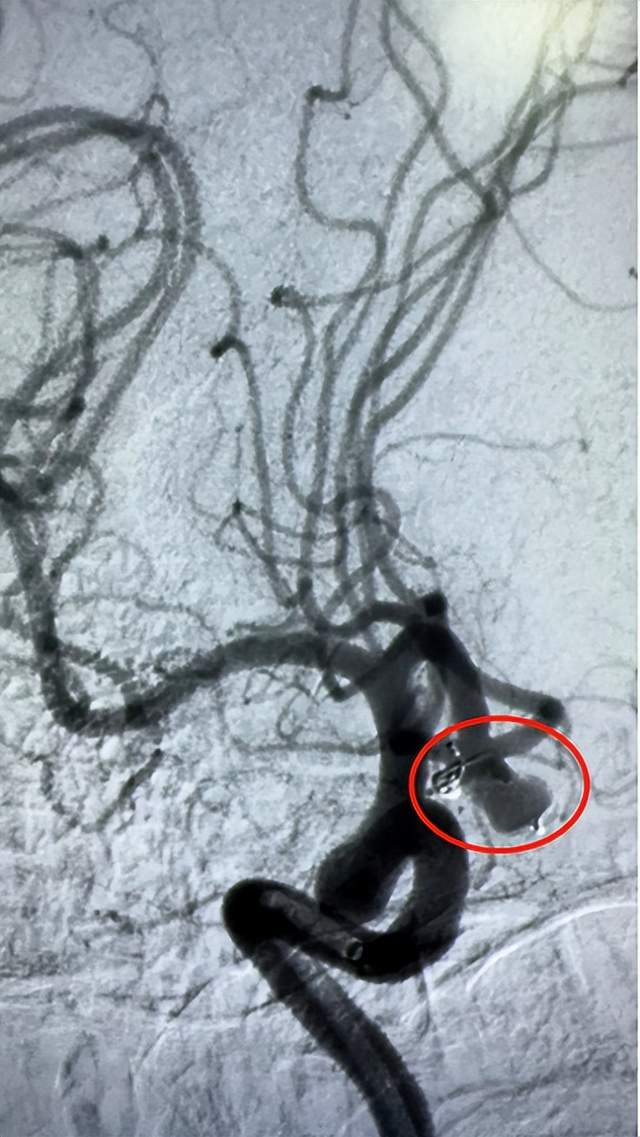

术中图片

术后图片

术后动脉瘤腔造影剂滞留明显,子囊未显影,颅内血管通畅。